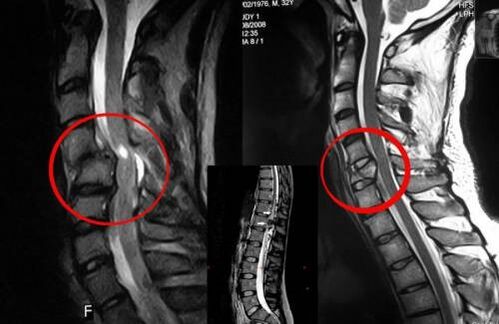

Compressione del midollo spinale indicazione all'intervento chirurgico

Quando è necessario un intervento chirurgico?

Se l'osteocondrosi cronica della colonna vertebrale si è sviluppata negli adulti e la terapia conservativa non aiuta, si ricorre a misure terapeutiche radicali. L'intervento chirurgico è necessario anche nei seguenti casi:

• sublussazione vertebrale;

• ernia;

• compressione acuta del midollo spinale;

• deformità spinale.